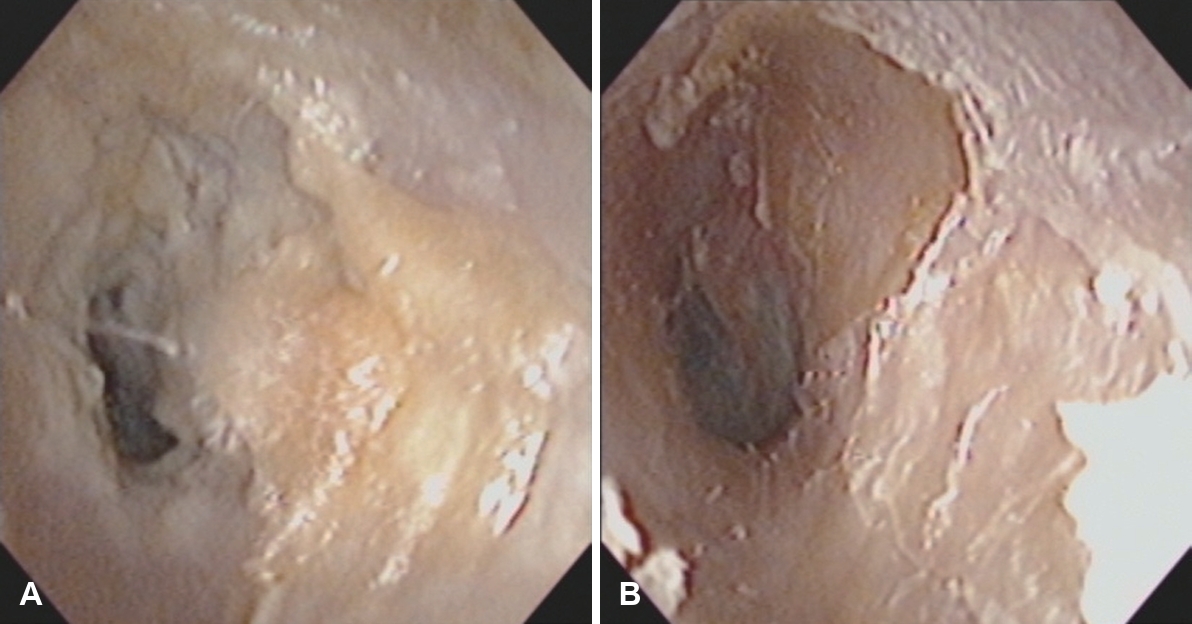

단독 외이도성형술이 모든 이루 환자에게 적용되는 것은 아니다. 고막 천공이 크거나 만성 감염, 진주종 등 중이 병변이 동반된 경우에는 고실성형술이나 유양돌기절제술과 같은 근본적 치료가 우선되어야 한다. 그러나 이런 환자에서도 수술 전 외이도 입구가 좁아 이루 배출이 어려운 경우, 중이 수술과 외이도성형술을 병행해 수술 직후 건조 유지와 환기 기능을 향상시킬 수 있다(Fig. 4).